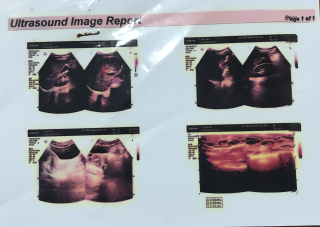

O Hoàng Thị Thư sinh năm ngày 10/2/1984. O bị ung thư vú vào viện mổ ngày 17/10/2025 trong tình trạng khối u đã lan rộng và bị vỡ, O đang trong liệu trình hoá trị nhưng O đã xin ngưng điệu trị vì do sức khoẻ đã quá yếu, bệnh đã di căn (giai đoạn cuối). Hoàn cảnh gia đình đặc biệt khó khăn, không có điều kiện kinh tế, O không có chồng, không có con hiện tại ở nhờ nhà em gái không ai chăm sóc (gia đình em gái cũng khó khăn và đang đi làm xa ở Hà Nội), bản thân O lắng không đủ khả năng lo liệu hậu sự cho mình khi qua đời. Nguyện vọng của O là xin giúp đỡ một áo quan để khi nhắm mắt xuôi tay O được an nghỉ. Sđt O Thư: 0977146168

Chị tên Hoàng Thị Thư. Sn 1984 Chị bị ung thư Vú đã mổ nhưng vì hoàn cảnh gia đình quá khó khăn không có vô thuốc hoá trị. Sau mổ chỉ uống thuốc lá nam nên bệnh tái phát, chị đang ở nhờ nhà em gái ở địa chỉ xóm Xuân đông, Bích hào, Nghệ an. Đt: 0977146168. Hiện tại chị phải vật lộn với những cơn đau ngày một dày hơn.

Vì đau quá nên hôm nay chị đi khám và được bác sĩ thông báo khối u đã di căn nhiều nơi bệnh đã sang giai đoạn cuối. Không có tiền chỉ chỉ lấy thuốc giảm đau rồi ra về trong nước mắt.